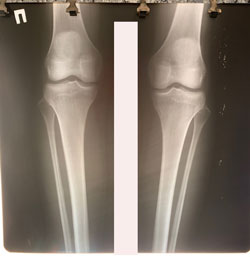

Исходник - 18 лет.

Дата операции 20.10.2020

Диагноз Варусная деформация голеней + Ротация с обеих сторон